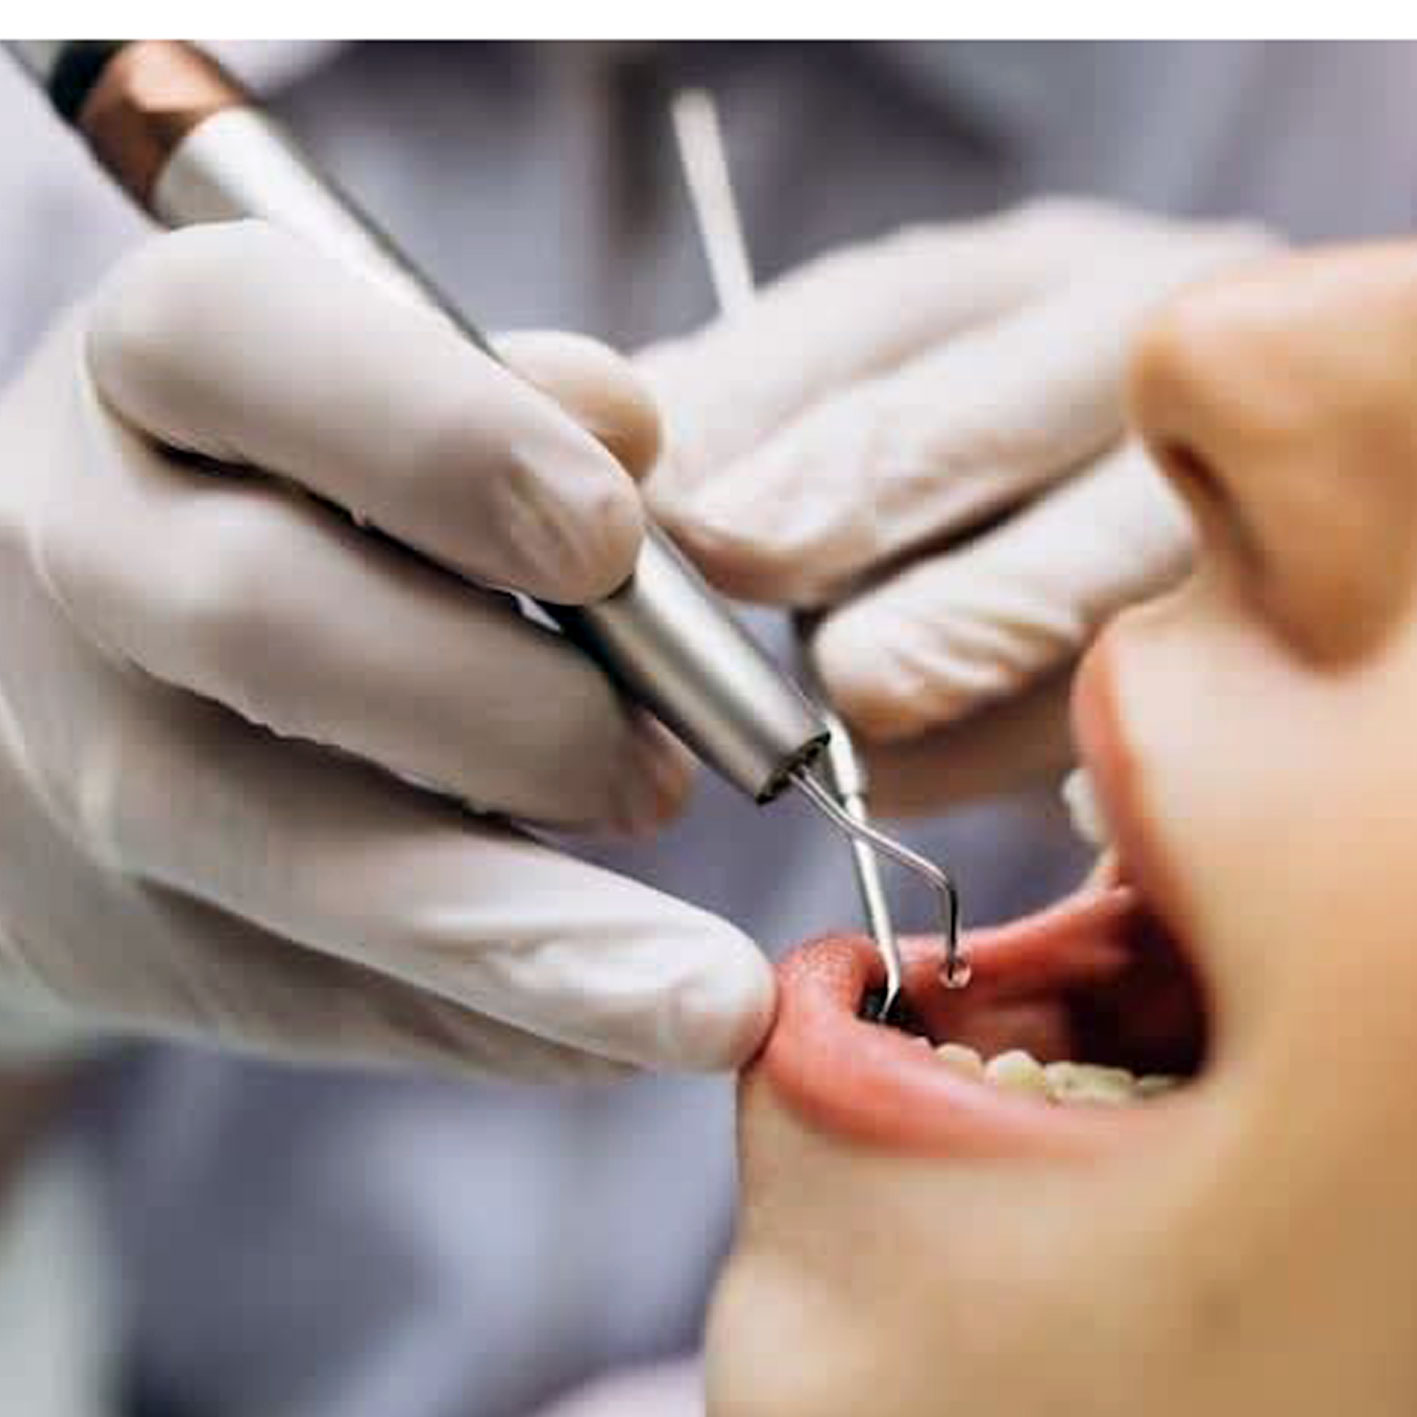

- عصب کشی دندان

چه زمانی نیاز به عصب کشی دندان تشخیص داده می شود